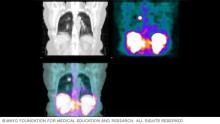

SPECT scan results picture

SPECT scan results

SPECT scan results can be in color or shades of gray. The varying shades or colors show which cells in the body are absorbing more or less of the radioactive tracer. This scan includes images of the kidneys, liver and spleen.

A radiologist or healthcare specialist with advanced training in nuclear medicine will study the results of your SPECT scan and send them to your healthcare team. Pictures from your scan may show colors that tell your team what areas of your body absorbed more of the radioactive tracer and which areas absorbed less. For instance, a brain SPECT image might show a lighter color where brain cells are less active and darker colors where brains cells are more active. Some SPECT images show shades of gray, rather than colors.